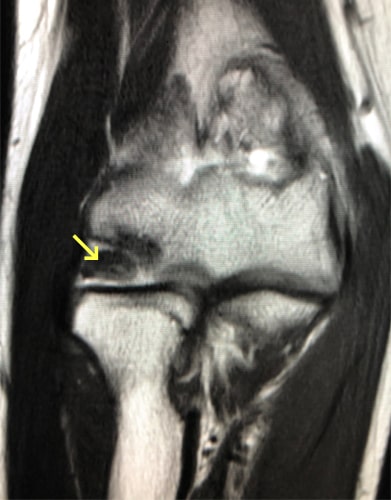

外側型の離断性骨軟骨炎写真1 外側型の離断性骨軟骨炎写真2

外側型の離断性骨軟骨炎

野球肘には内側型と外側型があります。内側型は軟骨が靭帯に引っ張られることにより痛みが発生し、多くは数週間の投球中止と正しいフォームを身に付けることで治ります。一方、外側型は離断性骨軟骨炎と呼ばれ、投げ方や投球数に限らず発生します。初期であれば保存的な治療で障害を残さず治りますが、進行すると手術が必要になったり、肘の動きが制限されて野球を続けることが難しくなります。